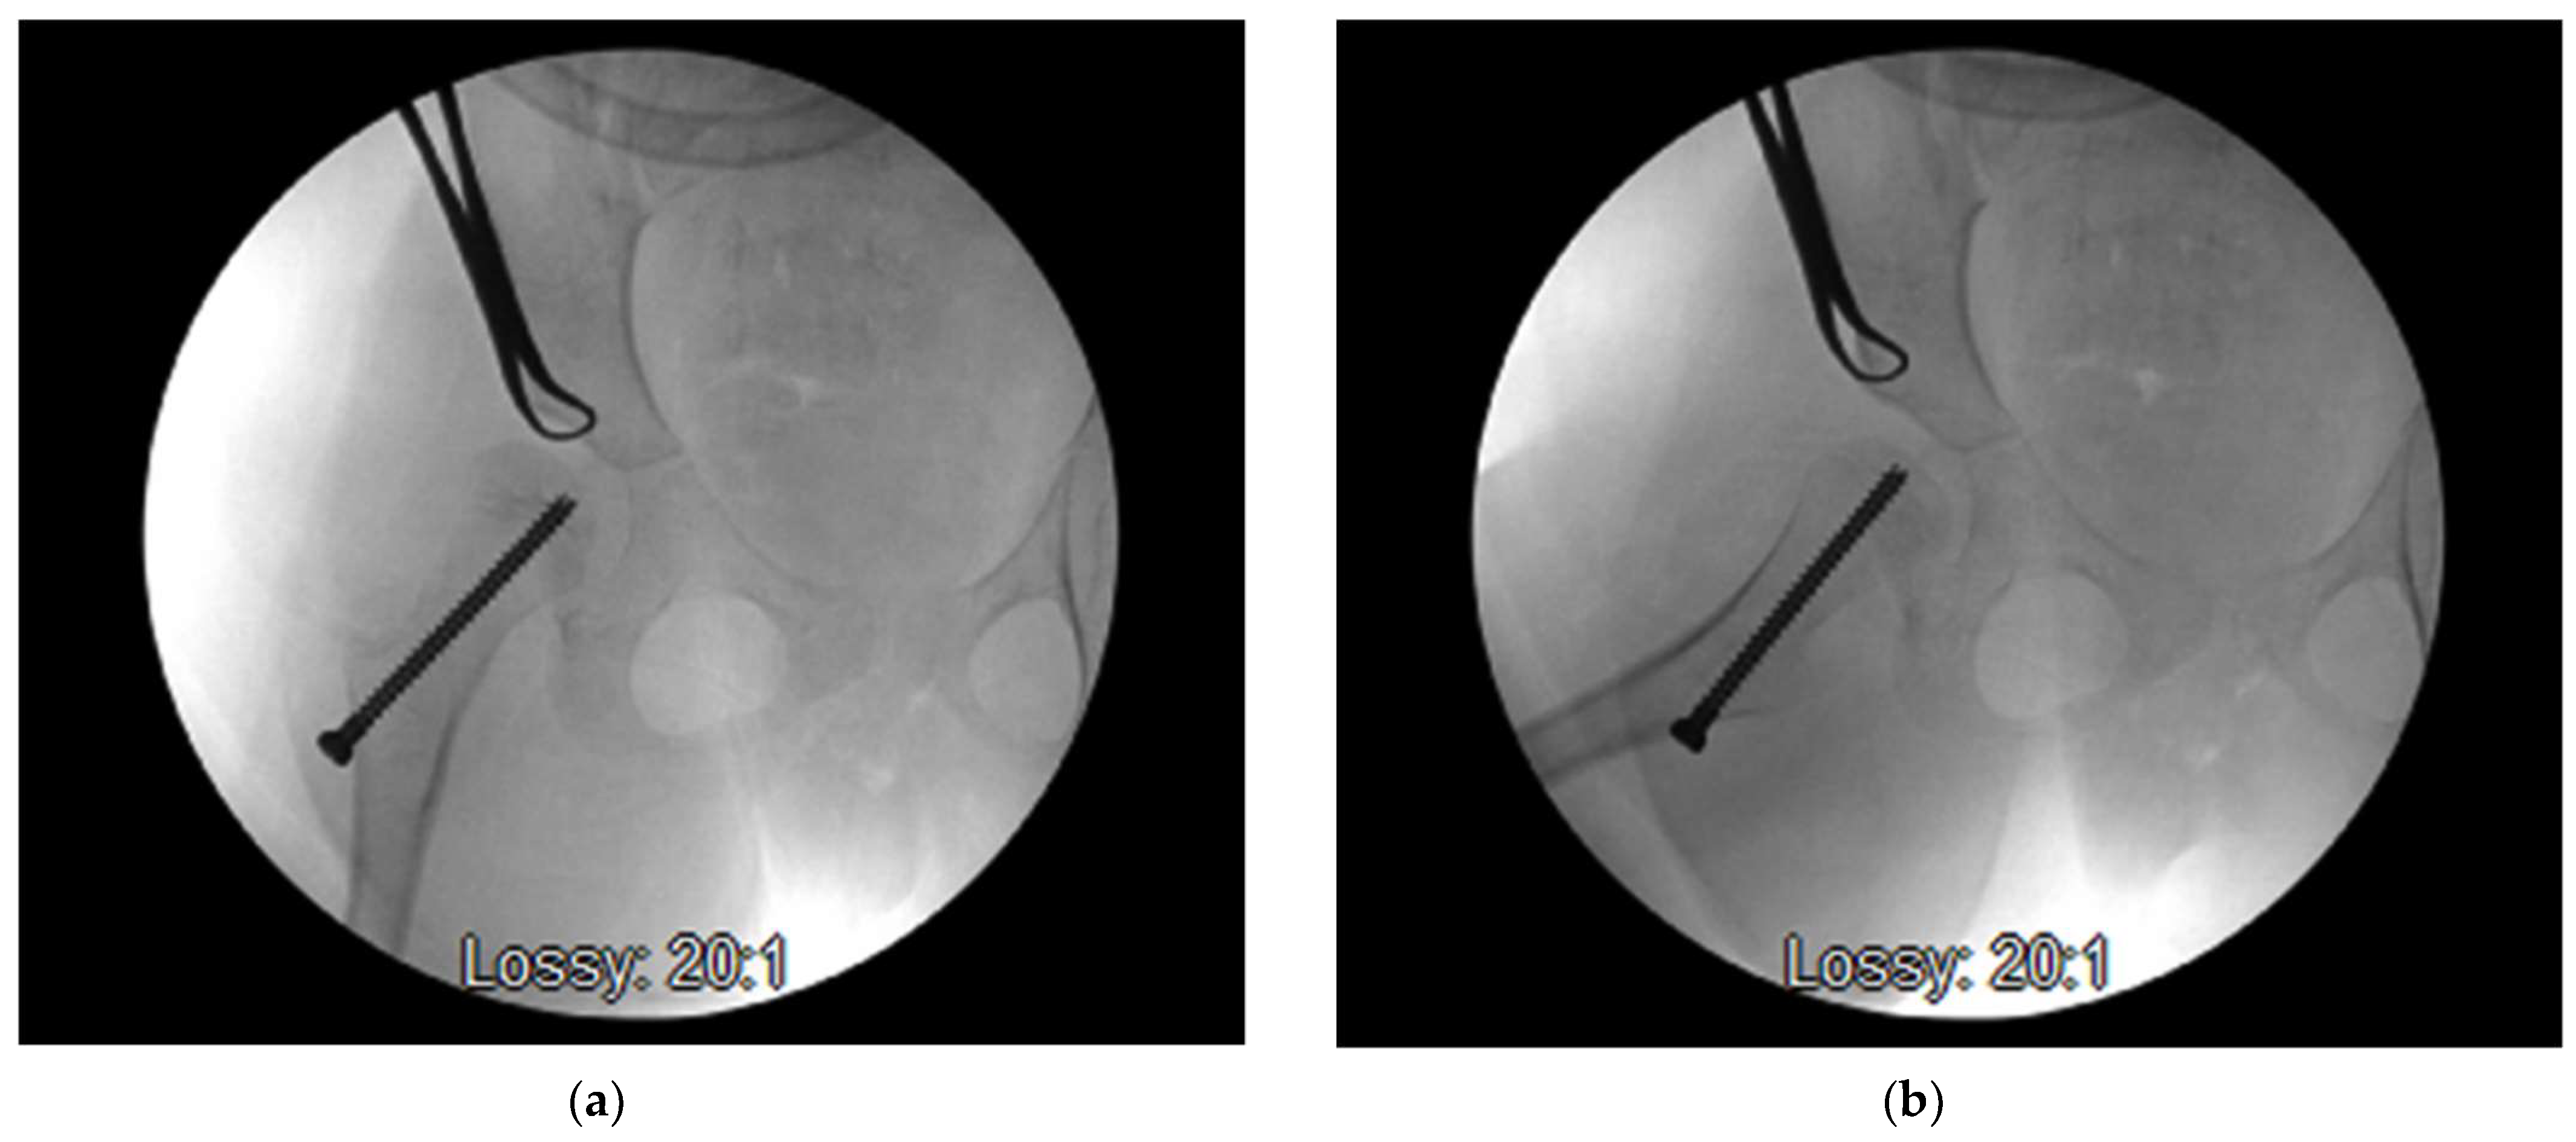

- Hsu, P.-J.; Wu, K.-W.; Lee, C.-C.; Lin, S.-C.; Kuo, K.N.; Wang, T.-M. Does screw position matter for guided growth in cerebral palsy hips? Bone Jt. J. 2020, 102, 1242–1247. [Google Scholar] [CrossRef]